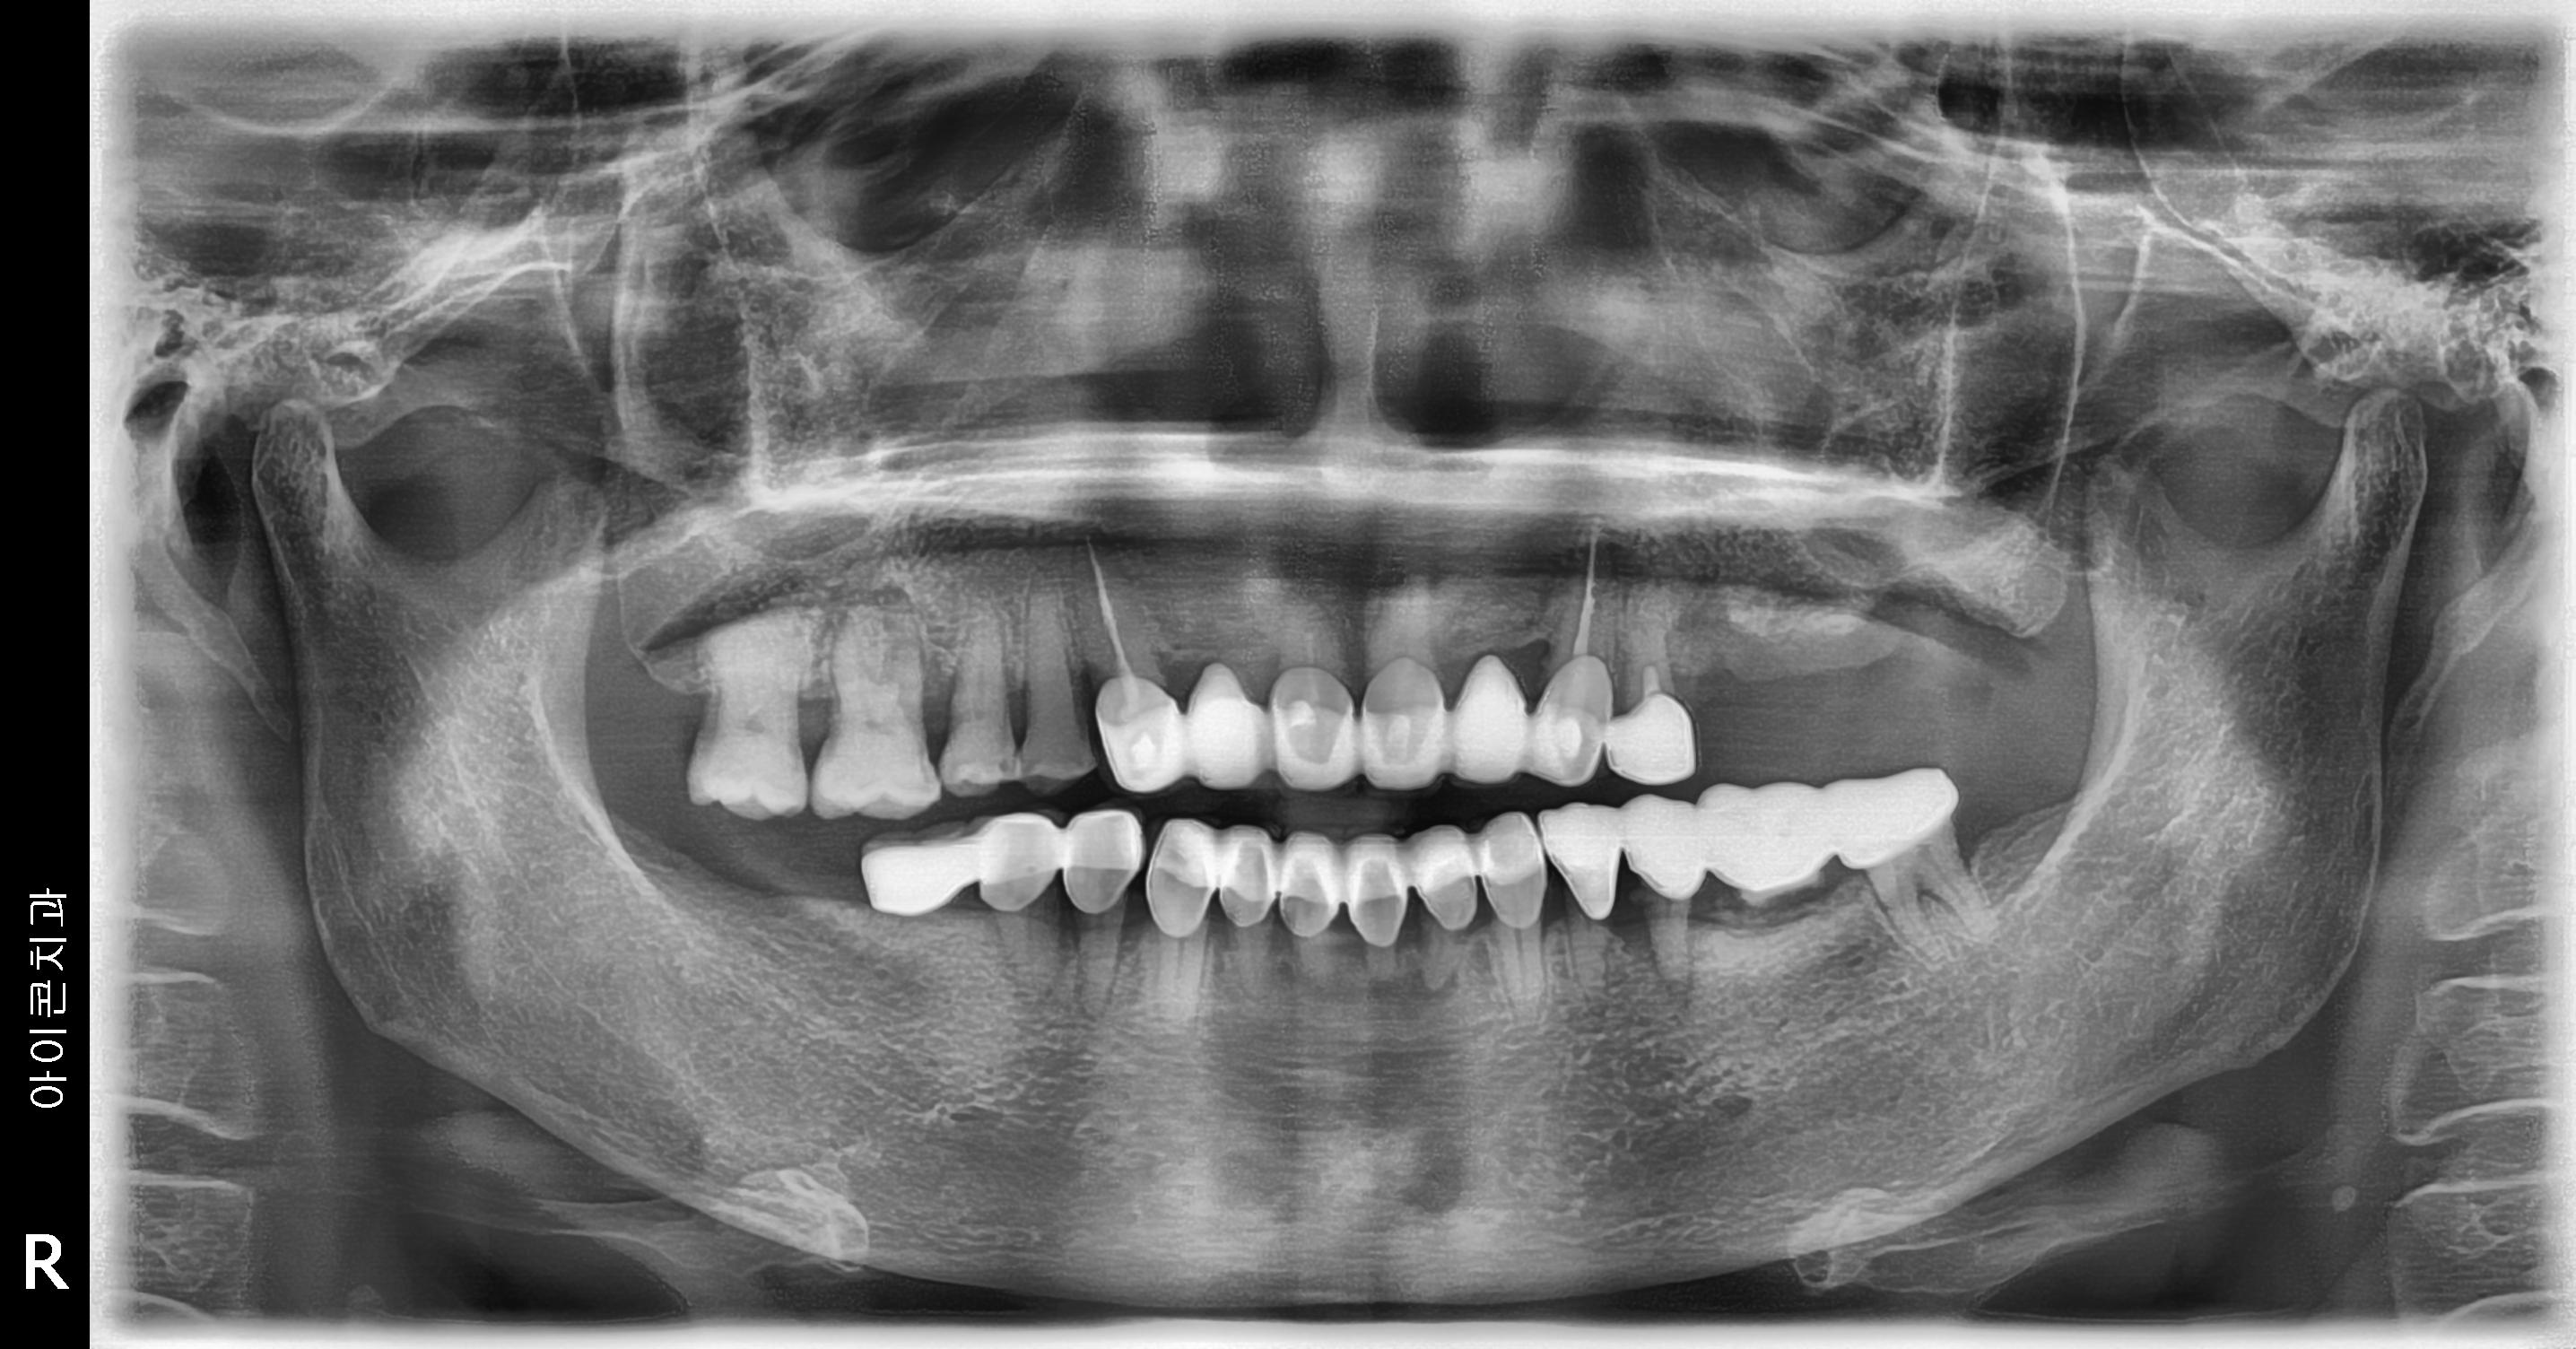

수술 전

수술 후

상하악 구치부 임플란트 식립사례

전후사진